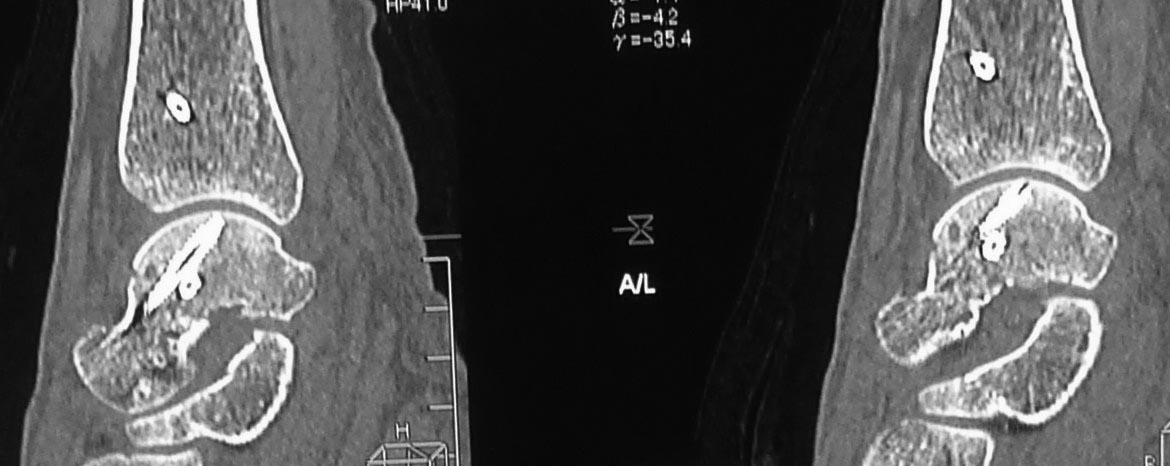

Вероятнее всего, речь изначально шла о не устраненном во время операции

вывихе проксимального фрагмента таранной кости. Во вложении похожий

случай, оперированный 10 дней назад (с послеоперационными снимками). Для

сравнения стрелками на двух рентгенограммах показан нависающий над

пяточной костью вывихнутый фрагмент таранной кости. На компьютерной

томограмме видно гораздо лучше. Так что о живом подтаранном суставе при

сохраняющемся подвывихе говорить не приходится. Кстати, остеотомия